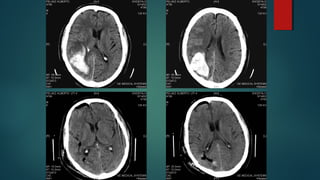

Este documento es el programa para un taller de imágenes del curso de emergencia 2015 impartido por el Dr. Víctor Delgado. El taller se centra en el uso de imágenes médicas para el diagnóstico y tratamiento de pacientes en coma traumático según la base de datos de Marshall. El Dr. Delgado es el único instructor repetido a lo largo del documento.